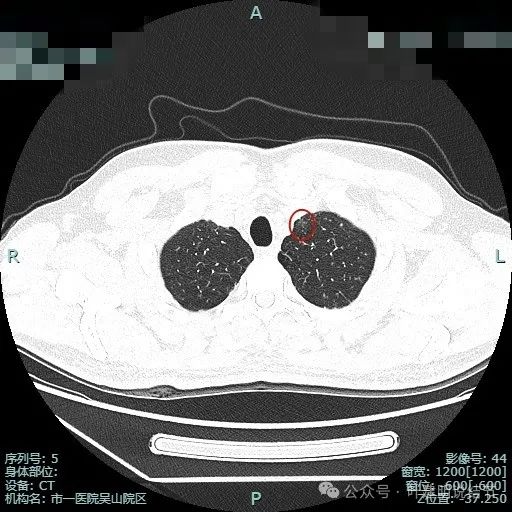

先来看两肺多发结节的总体情况:

病灶1:左上叶肺尖淡磨玻璃影,轮廓稍显模糊,少许慢性炎或肺泡间隔增宽可能性大。

病灶2:右上肺胸膜下微小磨玻璃结节,表面欠光滑,倾向肺泡上皮增生之类的病变,目前不十分确切,但风险总是低的。